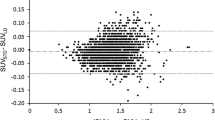

The PET data from each of the 15 patients were reconstructed using the μ-mapCT, μ-mapDX, μ-mapUTE, μ-mapANN, μ-mapR2, μ-mapTMP, and μ-mapATL for AC. The reconstructed PET data using μ-mapCT for AC was used as reference to calculate the En. The average En measured in those regions related to AD is shown in Fig. 3, together with the regions that were analysed. The variability was calculated as the standard deviation between patients and brain hemispheres. The area between ±5 % error is indicated in Fig. 3. The numerical values are shown in supplemental Table 3.

The analysis showed that μ-mapDX produced the most inaccurate results, compared to all the other methods, including the μ-mapUTE also available in the scanner [7, 8, 28], with an average En of -14.9 %, compared to −8.9 % measured with the μ-mapUTE. Among the four new methods compared in this study, the average errors in the analysed regions were 2.13, 1.04, −1.36, and −0.21 % for the μ-mapANN, μ-mapR2, μ-mapTMP and μ-mapATL, respectively, which means that the average FDG uptake was slightly overestimated with μ-mapANN and μ-mapR2 and slightly underestimated with mapTMP and μ-mapATL. The positive sign of the first two methods can be interpreted as an overestimation of the amount or density of the bone structure. The ANN-based method produced slightly higher errors than the other methods in the parietal region and the precuneus regions, in particular the parietal superior showed an En>5 %, which was over the limit considered as acceptable in this study. For completeness we show in supplemental Fig. 4 the absolute error measured in the same AD-related regions, and their numerical values in supplemental Table 4. The average absolute error with μ-mapDX and μ-mapUTE was below −1.0 kBq/mL, while the four new methods resulted in average errors of −0.04–0.24 kBq/mL.